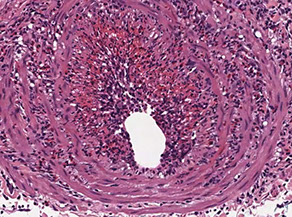

Temporal (Giant cell) aortitis/arteritis

Micro: Fragmented elastic fibers, giant cell / granulomatous (macros and lymphos) response and intimal thickening which reduces lumen

- giant cells not required for temporal arteritis (in ~75%), only destruction of internal elastica with inflammation

Giant cell arteritis of the breast. The vessel wall has been replaced by granulomatous inflammation. The process has compressed the vessel lumen to near-complete obstruction. A giant cell is shown in this field. B, Giant cell arteritis of the breast. Granulomatous inflammation and fibrinoid necrosis are shown within the wall of this vessel. C, Giant cell arteritis of the breast. The special elastin stain highlights the fragmentation of the internal elastic

lamina in this vessel (hematoxylin-eosin, original magnifications320 [A and B]; original magnification320 [C]).